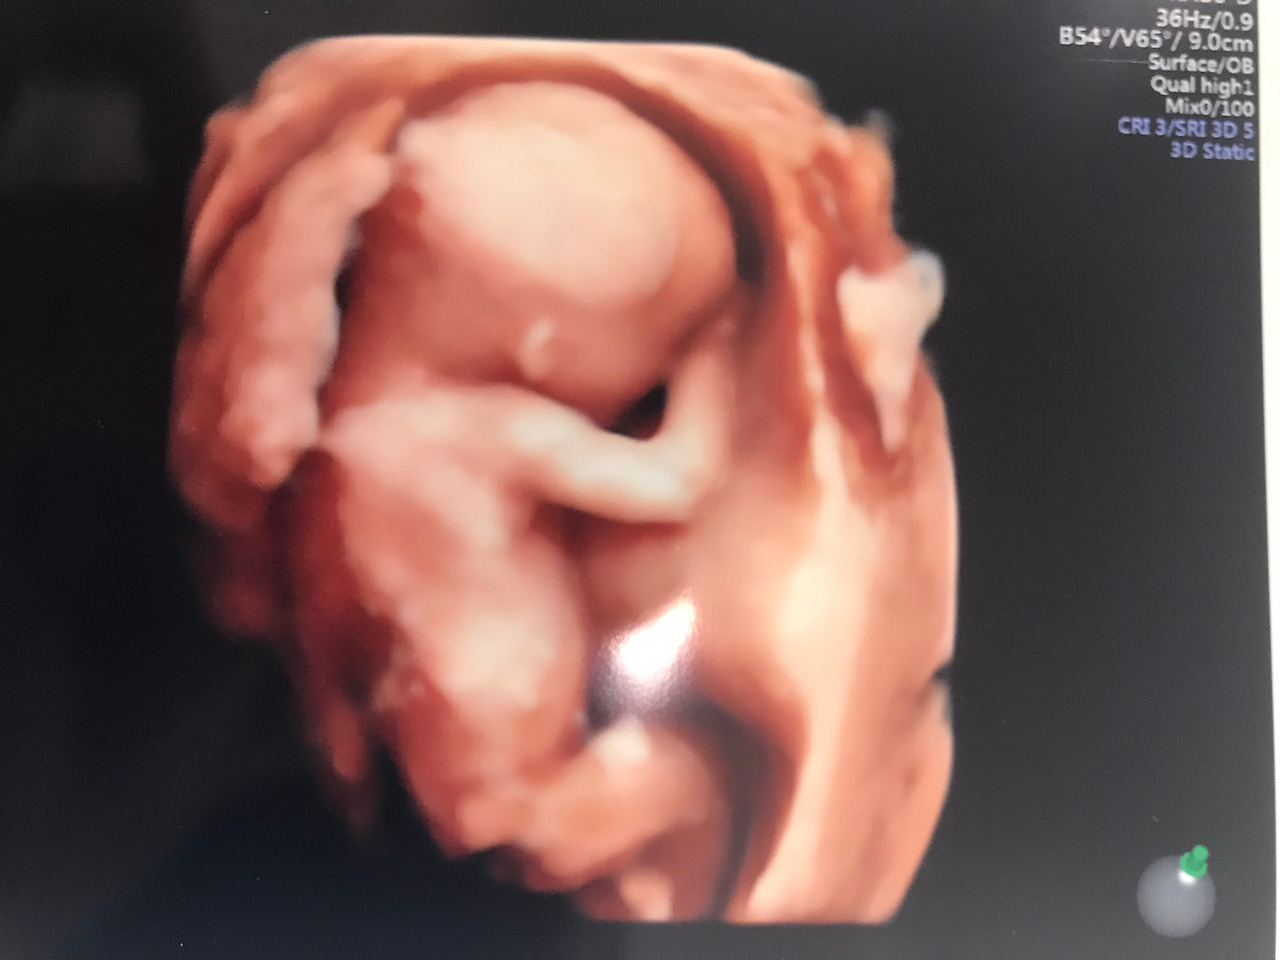

여전히 얼굴은 가리고 보여주지 않던 우리 딸(16주)

그래도 이제는 재하가 태동을 시작했다. 가만히 배를 만져보고 있으면 아이가 올록볼록하며 움직이는 게 느껴진다. 불행하게도 재하는 엄마를 닮아 많이 움직이고 특히 밤에 더 뛴다. 우리 엄마가 말하기를 나는 하루에 한 번도 태동을 안 할 때도 있었다는데 재하는 아닌가 보다. 부디 야행성인 것만 엄마 따라가지 말고 생긴 것도 엄마 닮았으면 하는 마음이 있다. 그리고 다음 주에는 부디 손으로 가리지 말고 얼굴도 좀 보여줬으면 좋겠다.